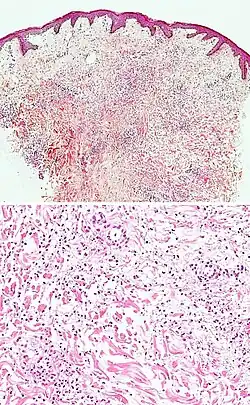

| Secondary syphilis | Various, but often one or a combination of:[21]

|

| Kaposi’s sarcoma in patch stage | The patch stage typically shows irregular proliferation of jagged vascular channels in the dermis below an integral epidermis. The so-called promontory sign is sometimes found in patch stage lesions and denotes vascular spaces surrounding pre-existing blood (see image).[23]